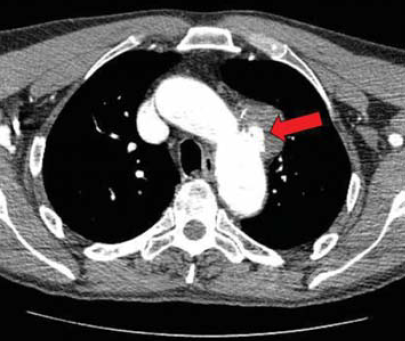

3. ábra.

PAU a proximalis aortaív hátsó felszínén.